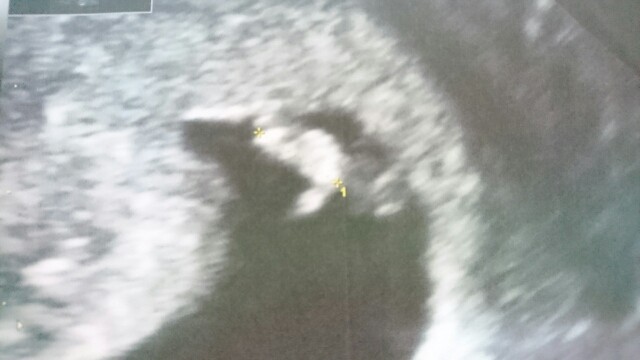

4t6d nie bylo a 6t0d juz bylo widac cos w srodku pecherzyka. Wiec w tak zwanym miedzyczasie.

Sliczna rybkaMaleństwo z ostatniej pierwszej wizyty. Serduszko już biło. Kolejna mam 2.05. Koło maleństwa jest guz - polip, mięśniak będziemy kontrolować.